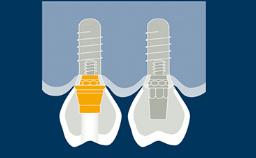

Prosthodontically driven implant planning ensures that implant placement is compatible with the desired end result, which is a key factor for successful outcomes in implant therapy.

Digital technologies now available in the field of implant dentistry facilitate prosthodontically driven implant planning. Benefits of these technologies include significant improvements in patient assessment and treatment planning, allowing clinicians to position supporting implants with a high degree of accuracy.